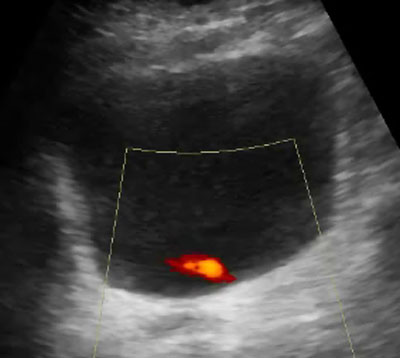

Jet urétéral normal en Doppler énergie